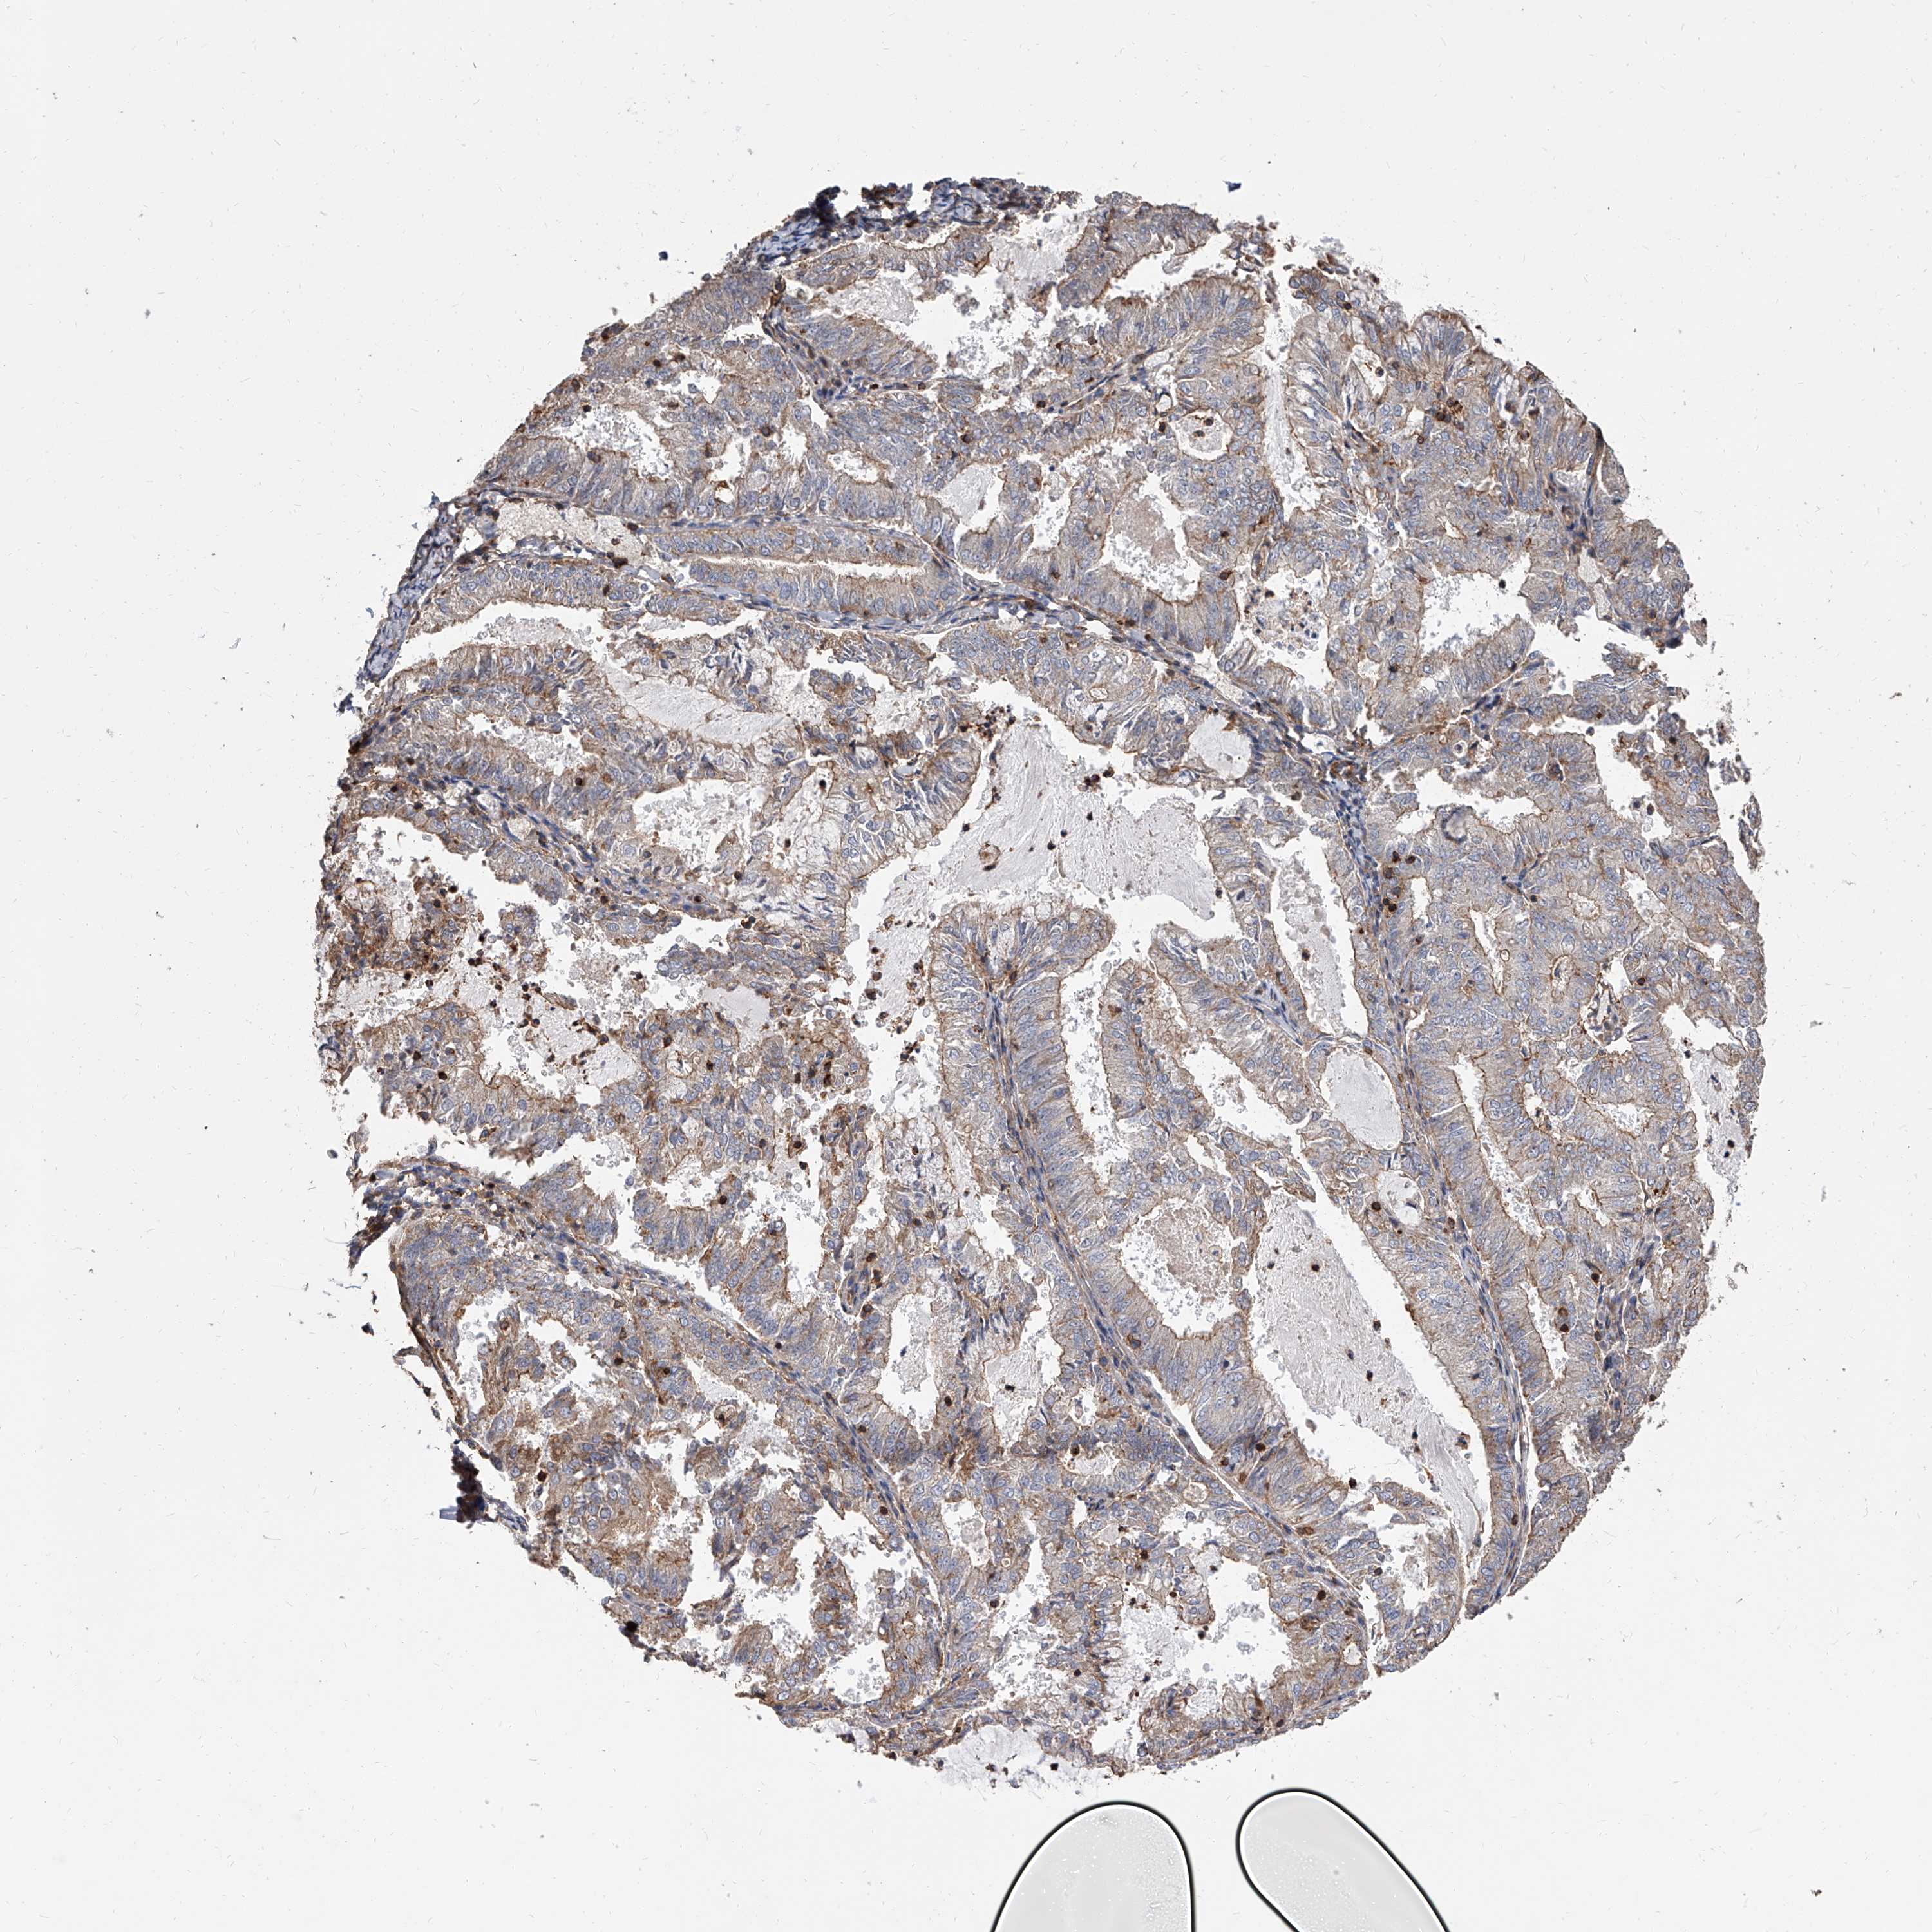

ENDOMETRIAL CANCER - Protein expressioni

A mouse-over function shows sample information and annotation data. Click on an image to view it in a full screen mode. Samples can be filtered based on level of antibody staining by selecting one or several of the following categories: high, medium, low and not detected. The assay and annotation is described here.

Note that samples used for immunohistochemistry by the Human Protein Atlas do not correspond to samples in the TCGA dataset.

Antibody stainingi

Antibody staining in the annotated cell types in the current human tissue is reported as not detected, low, medium, or high, based on conventional immunohistochemistry profiling in selected tissues. This score is based on the combination of the staining intensity and fraction of stained cells.

Each image is clickable and will lead to virtual microscopy that enables deeper exploration of all samples and also displays staining intensity scores, fraction scores and subcellular localization as well as patient and tissue information for each sample.

Antibody HPA031090

Antibody HPA031091

Staining

High

Medium

Low

Not detected

Intensity

Strong

Moderate

Weak

Negative

Quantity

>75%

75%-25%

<25%

None

Location

Nuclear

Cytoplasmic/membranous

Cytoplasmic/membranous,nuclear

Adenocarcinoma, NOS